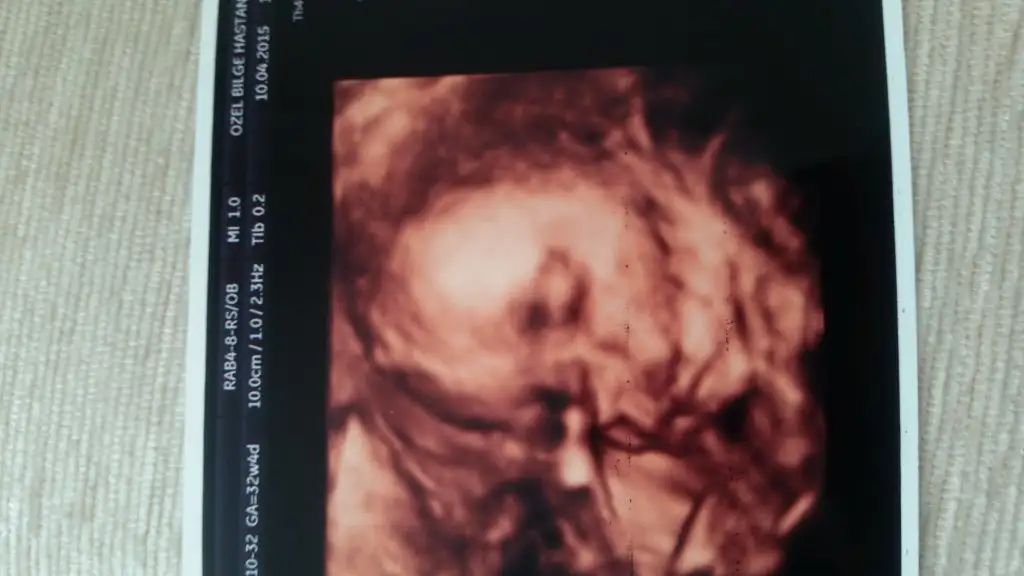

Maşallah yerimm seni bennn oyş kurban olduklarım32+4 de biiizzz:)